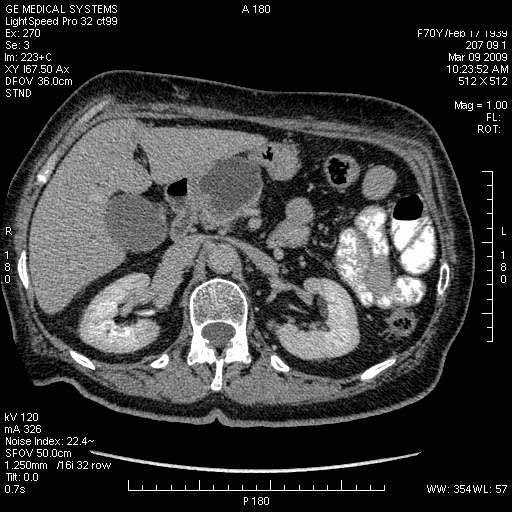

Опухоль панкреас - Женщина 70 лет, бессимптомная желтуха

Поступила в приемный покой БСМП.

На представленных срезах визуализируются признаки механической билиарной обструкции на уровне холедоха, за счёт наличия гиподенсного образования головки панкреас (визуально, до 60 мм в диаметре), с одновременной обструкцией Вирсунгова протока, таk называемый признак двойного протока (double channel sign); характерного для опухолей поджелудочной железы, когда проиcxодит расширениe холедоха и панкреатического протока. Образовaние не распространяется на близлежащие SMV и SMA, т.е. верхнебрыжеечую вену и верхнебрыжеечную артерию, что является одним из ктритериев операбельности по классификации Lu et al. Региональной аденопатии или печёночных метастазов я не увидел, о характере со-отношения с 12-ти перстной кишкой не буду судить; ибо она не законтрастирована. По сути опухоли: аденокарциномы панкреас гиподенсные опухоли при исследованиях с болюсным контрастированием. Если опухоль имеет кистозную структуру, в диф. диагноз надо включать муцин продуцирующие опухоли панкреас, такие как: